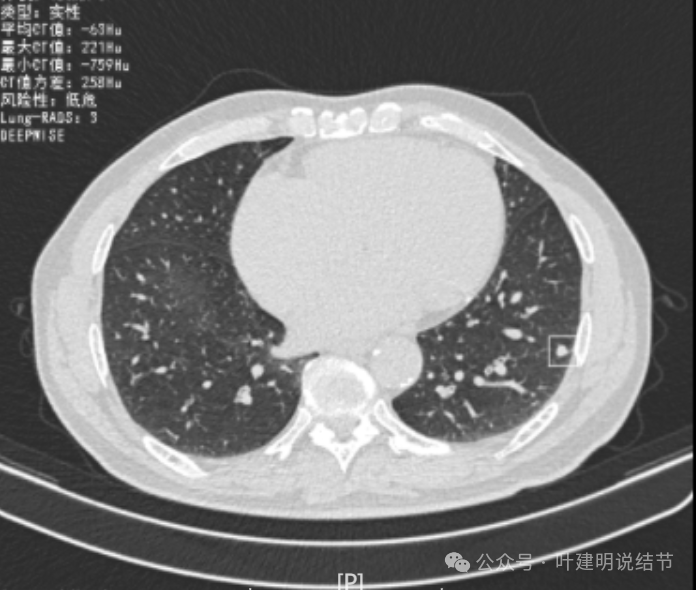

再看2022年8月复查时AI报告找出来的影像:

多是微小实性结节,主要的仍是右上与左下的这两处,较3月时无明显变化。而右下原来似有微小结节处这次并不明显。